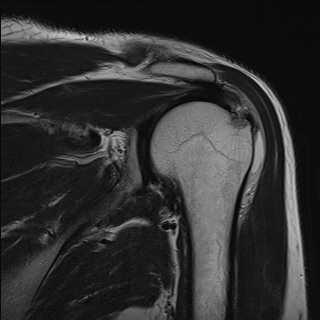

±Ø»ó°Ç³»Ãø Á¾´Ü¸é°Ë»ç¿¡¼­ ±Ø»ê°Ç ºÎÂøºÎÀÇ  ÀÛÀº ÆÄ¿­°ú Á¡¾×³¶ ºÎÁ¾ÀÌ °üÂûµÊ(±×¸² 2, 3).

±Ø»ó°Ç ÆÄ¿­, Á¡¾×³¶¿°, °ßºÀÇÏ °ñ±Ø